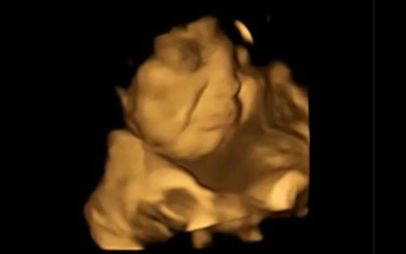

O echipă de oameni de știință a studiat ecografiile 4D a 100 de femei însărcinate și a descoperit că bebelușii expuși la arome de morcov au prezentat în mediul intrauterin reacții similare cu zâmbetul.

Cei expuși la arome de varză kale, în schimb, nu păreau să fie prea încântați și au fost surprinși afișând grimase.